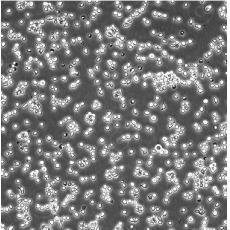

NAMALWA

產品名稱 NAMALWA

中文名稱 人Burkitt's淋巴瘤細胞

組織來源 Burkitt's淋巴瘤;女性

生長特性 suspension

形態(tài)特征 lymphoblast

傳代方法 Resuspending the cells in fresh medium at 5×10^5 viable cells/mL and subcultured at 2×10^6 cells/mL.

細胞描述 The cells contain the Epstein-Barr virus(EBV) genome.